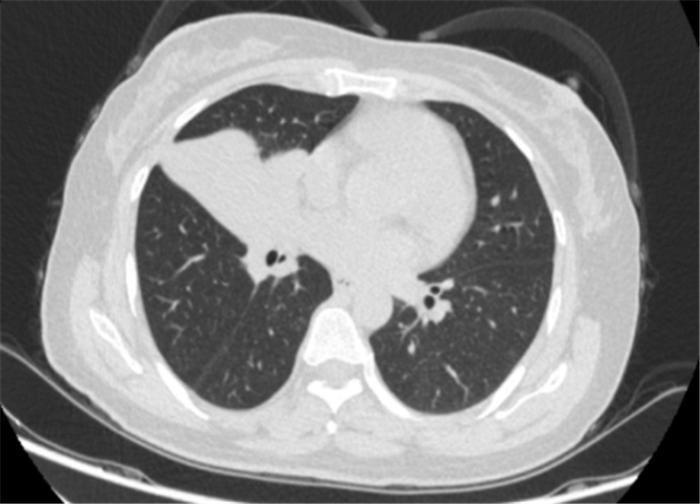

李女士(化名)年近50岁,因为咳嗽、咳痰两个多月到我院就诊。一经检查,发现她患有肺癌(右肺鳞癌并右侧肺门淋巴结转移),已经属于晚期(T3N1M0 IIIA)。

肺癌主要的组织类型是非小细胞肺癌(NSCLC),手术是治疗非小细胞肺癌的重要手段。然而,经过多学科会诊,李女士的病灶靠近心脏,加上手术对患者的身体状况要求也高,无法进行手术治疗。多学科专家反复讨论治疗方案,在和家属多次沟通下,最终选择由呼吸与危重症医学科采用免疫新辅助治疗,实现降期缩瘤再手术治疗。

经过4个周期的治疗后复查发现:李女士的病灶明显缩小,实现了降低肺癌分期。

患者治疗前基线胸部CT